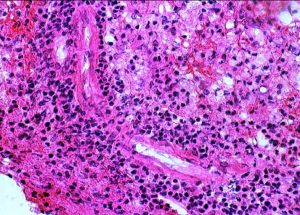

円形から楕円形の核腫大を伴う異型細胞がびまん性に増殖しています。核は水泡状のものが目立ちます。黄色の矢印は核分裂像を示します。大細胞性リンパ腫 large B cell lymphoma の特徴的なHE染色像です。

Ki-67染色によるMIB-1染色率は80%を超え,細胞の分裂増殖が激しいことを示します。リンパ腫増殖はとても早く,1週間単位でMRI上の腫瘍増大が認められます。

CD20陽性のB細胞リンパ腫でした。